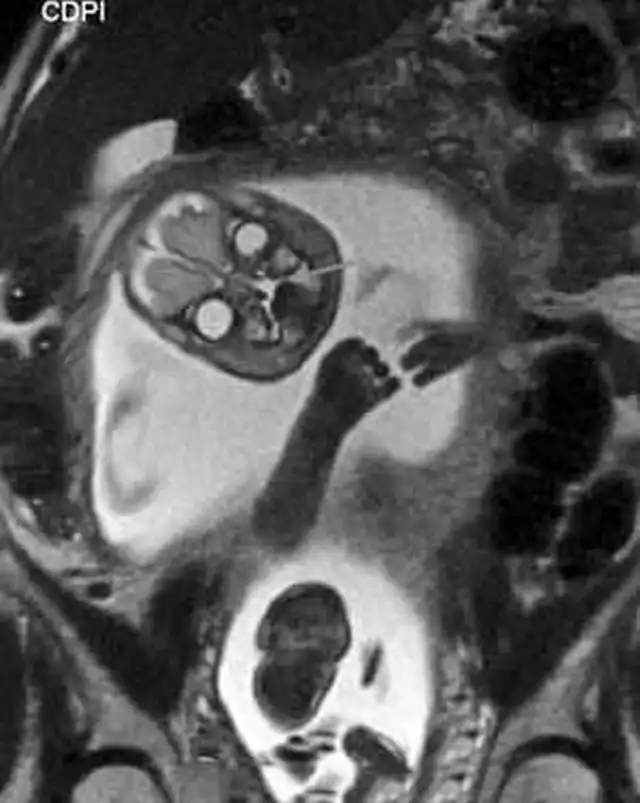

Всегда подмечал в голливудских фильмах такое клише: беременной девушке делают УЗИ, а потом показывают матери и отцу эмбриончик, после чего все начинают умиляться, охать и обниматься, несмотря на то, что на экране по сути ничего не видно. В которой раз можно убедиться в том, что в мелодрамах правды нет. Это подтверждают жуткие МРТ-снимки беременной женщины из реальной жизни. Честно скажу, мне это сегодня приснится. Впечатлительным я бы рекомендовал не смотреть.